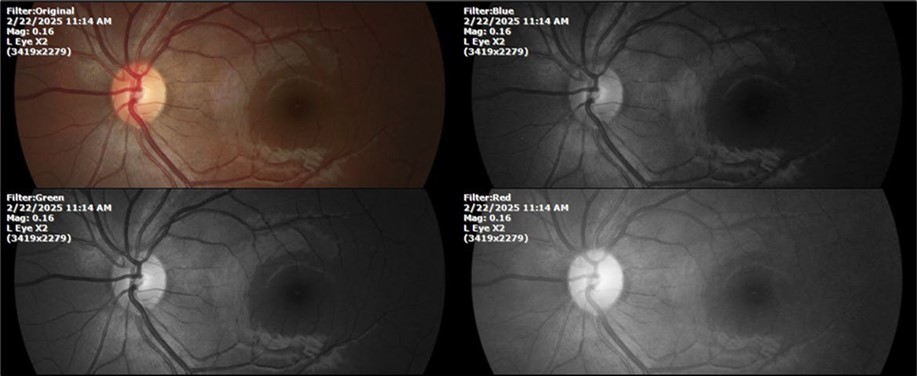

Figure 11.The photograph of the left eye does not show pathological data.

Figure 12. The photograph of the back of the eye, on the left side, shows a normal anatomy.